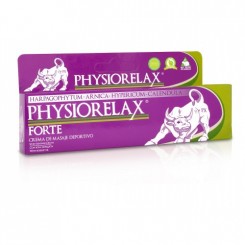

Ortopedia Deportiva

Hay 4 productos.